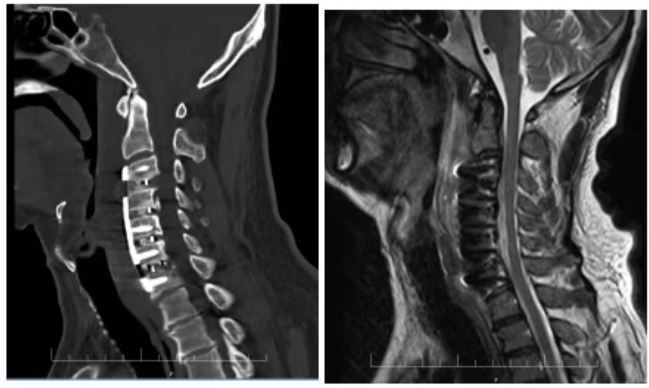

12月20日,在麻醉科的配合下,脊柱外科主任向伟能、副主任蒋成明医疗团队在中南大学湘雅医院脊柱外科吴天定教授的指导下顺利为赵先生完成颈椎前路可控前移融合术。术后患者四肢麻木无力感明显缓解,术后第二天即下床活动,患者及家属对治疗效果和医护人员贴心的服务非常满意。

前沿技术的前后对比图

向伟能主任介绍,颈椎前路可控前移融合术是由上海长征医院发明的一项“颈椎后纵韧带骨化物复合体前移(ACAF)”手术技术,顺利解决了后纵韧带骨化症不易治愈、术后瘫痪率高的世界性医学难题。